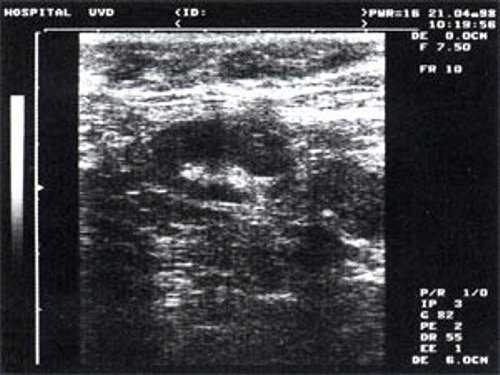

Мы выявили совершенно другую УЗ-картину состояния пальпируемых лимфатических узлов при динамической оценке у больных с синдромом иммунодефицита. Оцениваемые лимфатические узлы имели эхографические признаки доброкачественного процесса, в большинстве наблюдений их размеры превышали 2-2,5 см. При этом во всех случаях дифференцировались составные части лимфатического узла. Определялся узкий кортикальный слой и широкая гиперэхогенная сердцевина при сохранении овальной конфигурации и соотношении поперечного/переднезаднего более 1.

При повторных УЗ осмотрах на фоне массированной противовоспатительной терапии было отмечено увеличение числа лимфатических узлов вовлеченных в процесс активизации. При этом заметной перестройки эхоструктуры и уменьшения размеров в наблюдаемых лимфатических узлах отмечено не было (рис 4).

Рис. 4. Варианты изображения увеличенного лимфатического узла с УЗ-признаками доброкачественной аденопатии у больного с синдромом иммунодефицита.